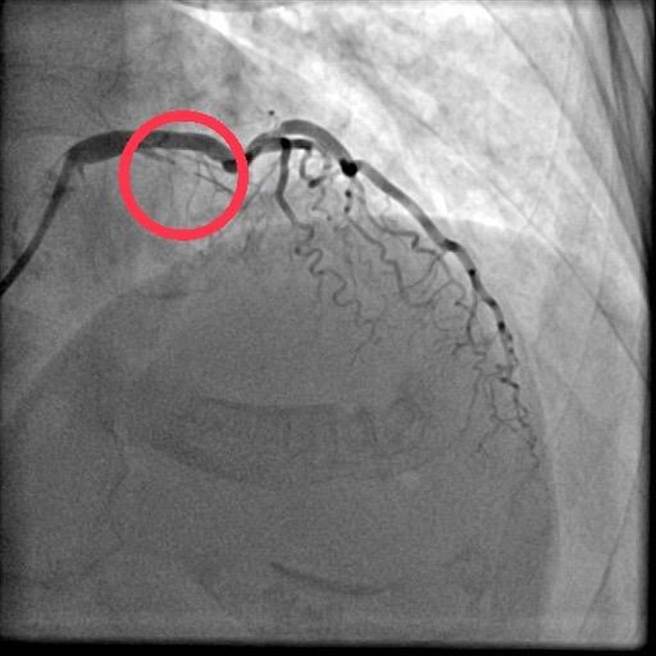

蔡贵嵚进一步说明,徐老太太于三义乡卫生所就医,心电图检查发现疑似心肌梗塞,医师透过联防网络之紧急转诊联繫管道即绿色通道,与部苗急诊团队进行跨院谘商,判断应转送治疗。同时医院启动急性冠心症医疗团队、预备心导管室、病床等,在病人抵达后,迅速完成检查及经皮冠状动脉扩张术,术后入住加护病房,3天后痊癒出院,转回住家附近的三义乡卫生所,继续追踪治疗,让病人和家属同感安心和便利。